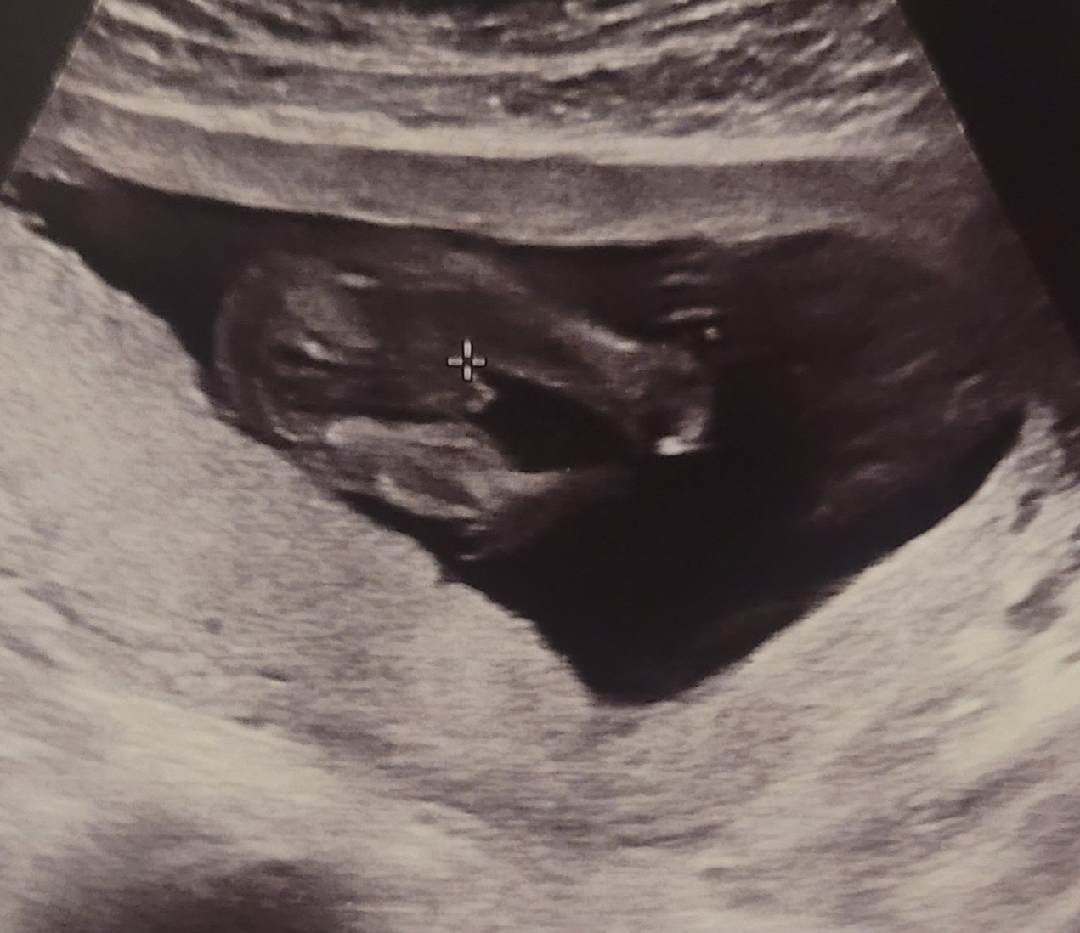

미사일모양이면 아들확률이높다고하네요~~

이정도면 아들 확정이겠죠?ㅋ

제곧내입니다ㅋ 16주1일 오늘 병원다녀왔는데ㅋ 애매하다고 나는 몰라 라고 원장님이 그러셨지만 다리사이 존재감 뿜뿜 맞는거겠죠?ㅋ 남편은 딸바랬는지 서운한 느낌이고ㅋ 저는 성격상 아들이 맞을것같아서 좋기도합니다ㅋ